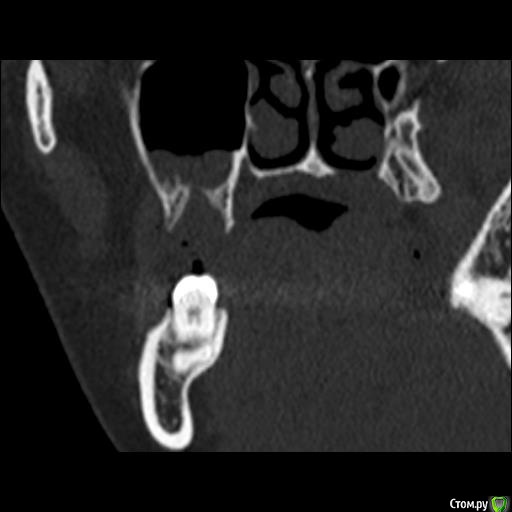

Юлия2386 Опубликовано 30 июля, 2020 Поделиться Опубликовано 30 июля, 2020 Добрый день, уважаемые врачи! Прошу вашей помощи, так как уже замучалась я конкретно. У меня уже 9 месяцев боли в правой стороне лица давящего характера. Давит на лоб, глаз, иногда висок. С декабря 2019 выявили фронтит-гайморит, проходила лечение у Лора и ещё невролога. Окончательного результата по выздоровлению за это время не достигнуто. Видимо это одномерный гайморит, так как постоянно какое-то воспаление формировалось у зубов 1.6;1.7;1.8. Многие стоматологи не видят проблем в зубе 1.6. Посоветовали удалить зуб 1.8 так как там был глубокий десневого карман. Удалила, а воспаление разрослось ещё больше (после удаления поцарапала щеку зубом 1.7, возможно из-за этого разрослось воспаление?!) После удаления прошёл месяц, а картина сейчас такая https://yadi.sk/d/ziceEN_jVZ9IkwВ итоге последний врач сказал, что все-таки проблема идёт от зуба 1.6, так как не запломбирован один канал, но из-за того что у зуба входят корни в гайморовых пазуху, лечить его не видет смысла, порекомендовал его удалить и через лунку вычиститься всю слизь, но он этим не занимается. Теперь я замешательстве и не знаю, что мне с этим делать, а самое ужасное, что глаз от этого болит( Уважаемые доктора, очень прошу вашей помощи, выскажите пожалуйста ваше мнение и может посоветуете к кому с этим можно обратиться в Москве. Ссылка на комментарий

wladdX Опубликовано 31 июля, 2020 Поделиться Опубликовано 31 июля, 2020 Представленная спиральная КТ не позволяет детально рассмотреть корневые каналы зубов и тп, чтобы получить какое-то внятное суждение.На уровне зубов 18, 17 и 16 есть локальное утолщение слизистой оболочки синуса и это всё, что из этого исследования можно выяснить. Адекватность обтурации корневых каналов зуба 16 оценить не представляется возможным (по крайней мере в моём понимании).Я бы порекомендовал сделать КЛКТ (конусно-лучевую компьютерную томографию), используемую в стоматологии. Ссылка на комментарий